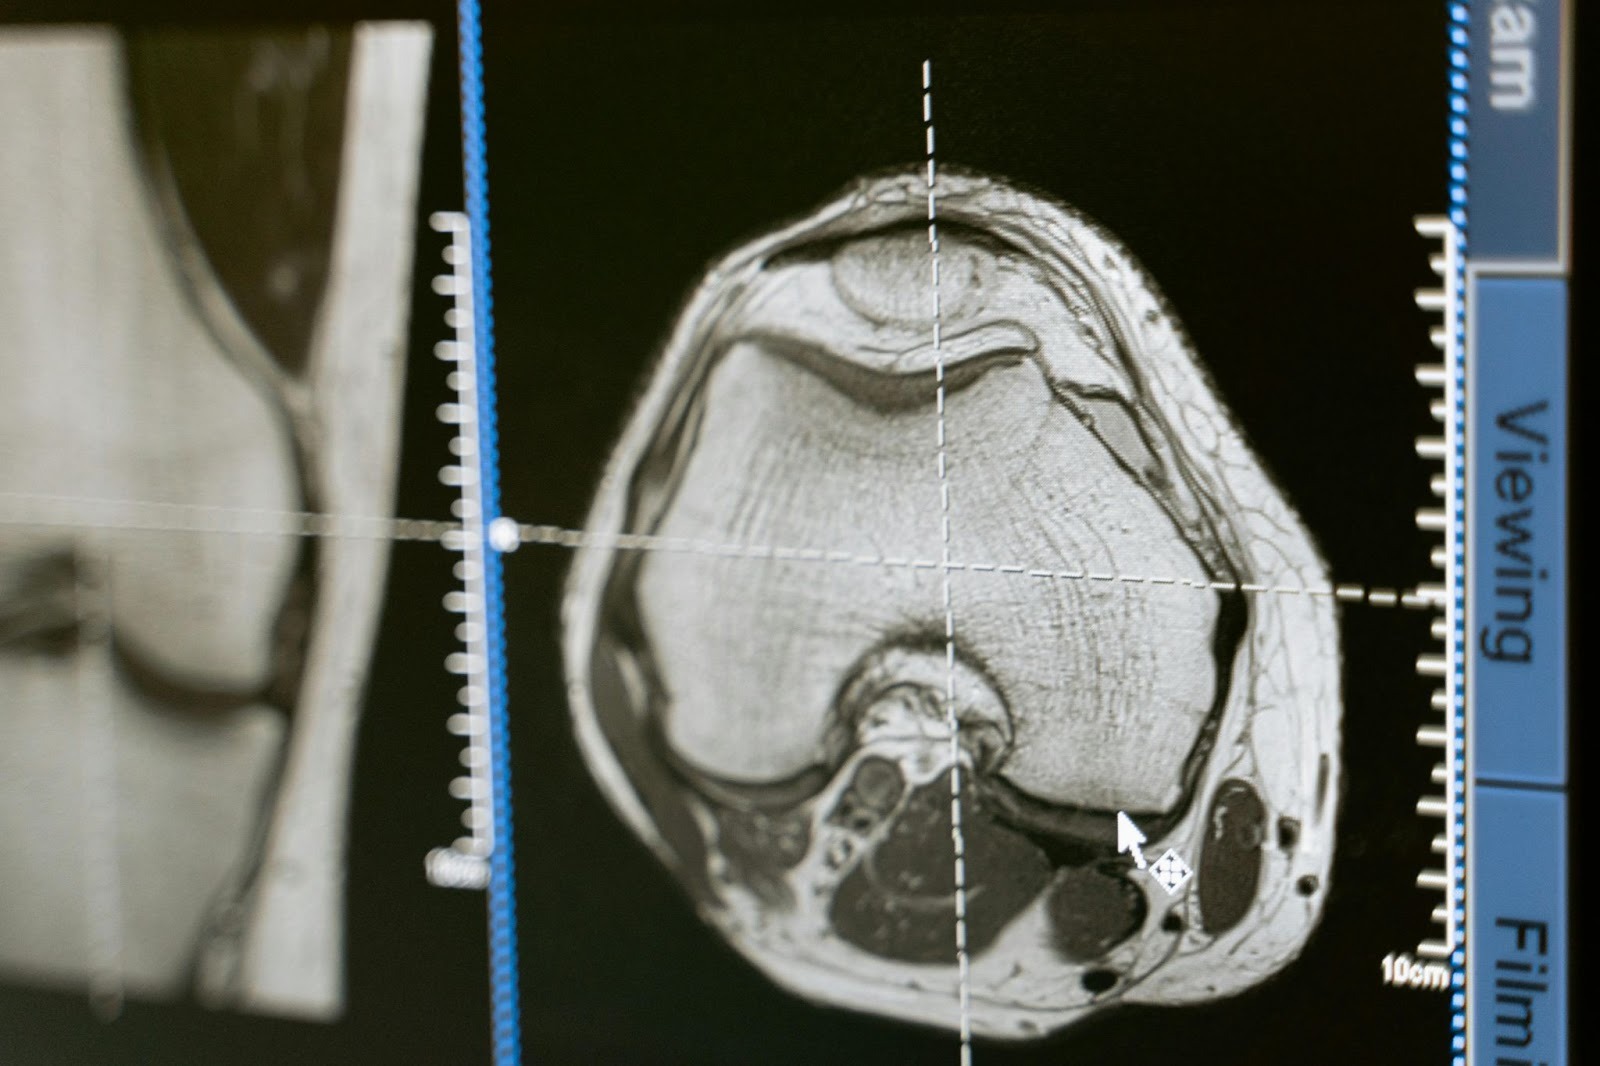

Advanced medical imaging uses different technologies to help healthcare professionals diagnose, monitor, and treat diseases. Common types include MRI, CT, PET, and ultrasound. Each offers unique views of the body.

Each imaging method requires specific training and skills. MRI is best for detailed images of soft tissues, CT provides cross-sectional views, and PET shows metabolic or functional activity. Professionals can cross-train in multiple areas to become more versatile and access more career opportunities.